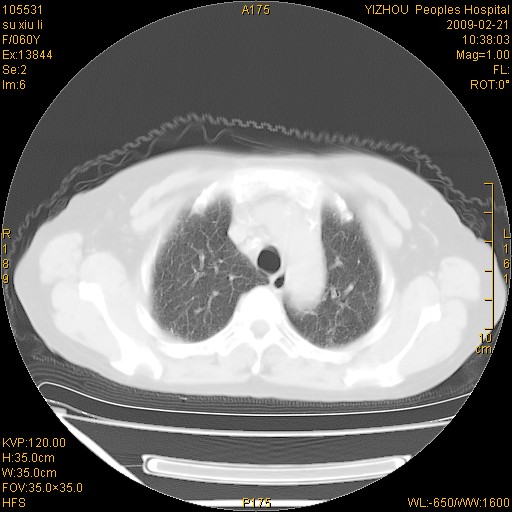

标题: CT18259:两肺间质纤维化? [打印本页]

标题: CT18259:两肺间质纤维化?

女,60岁,反复咳嗽1月。

两肺支扩,以肺为著合并双肺较广范纤维化病变。建议除外结核等病变。

间质性肺炎

两下肺支扩

符合间质感染,部分纤维化表现

特发性间质纤维化

特发性间质纤维化伴支扩!

间质性肺炎或特发性间质性肺炎